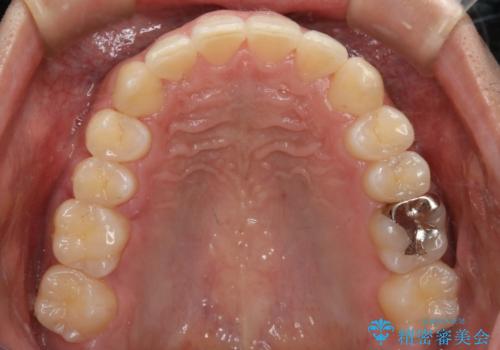

インビザラインで八重歯の治療

- 2年3ヶ月

マウスピースとマイクロインプラントを組み合わせることで、抜歯をしなくても歯並びを治すためのスペースを作ることができます。奥歯から順に移動させていくので前歯に変化が出るまでには時間がかかりますが、その分健康な歯を抜歯することなく理想的な歯並びを手に入れることができます。